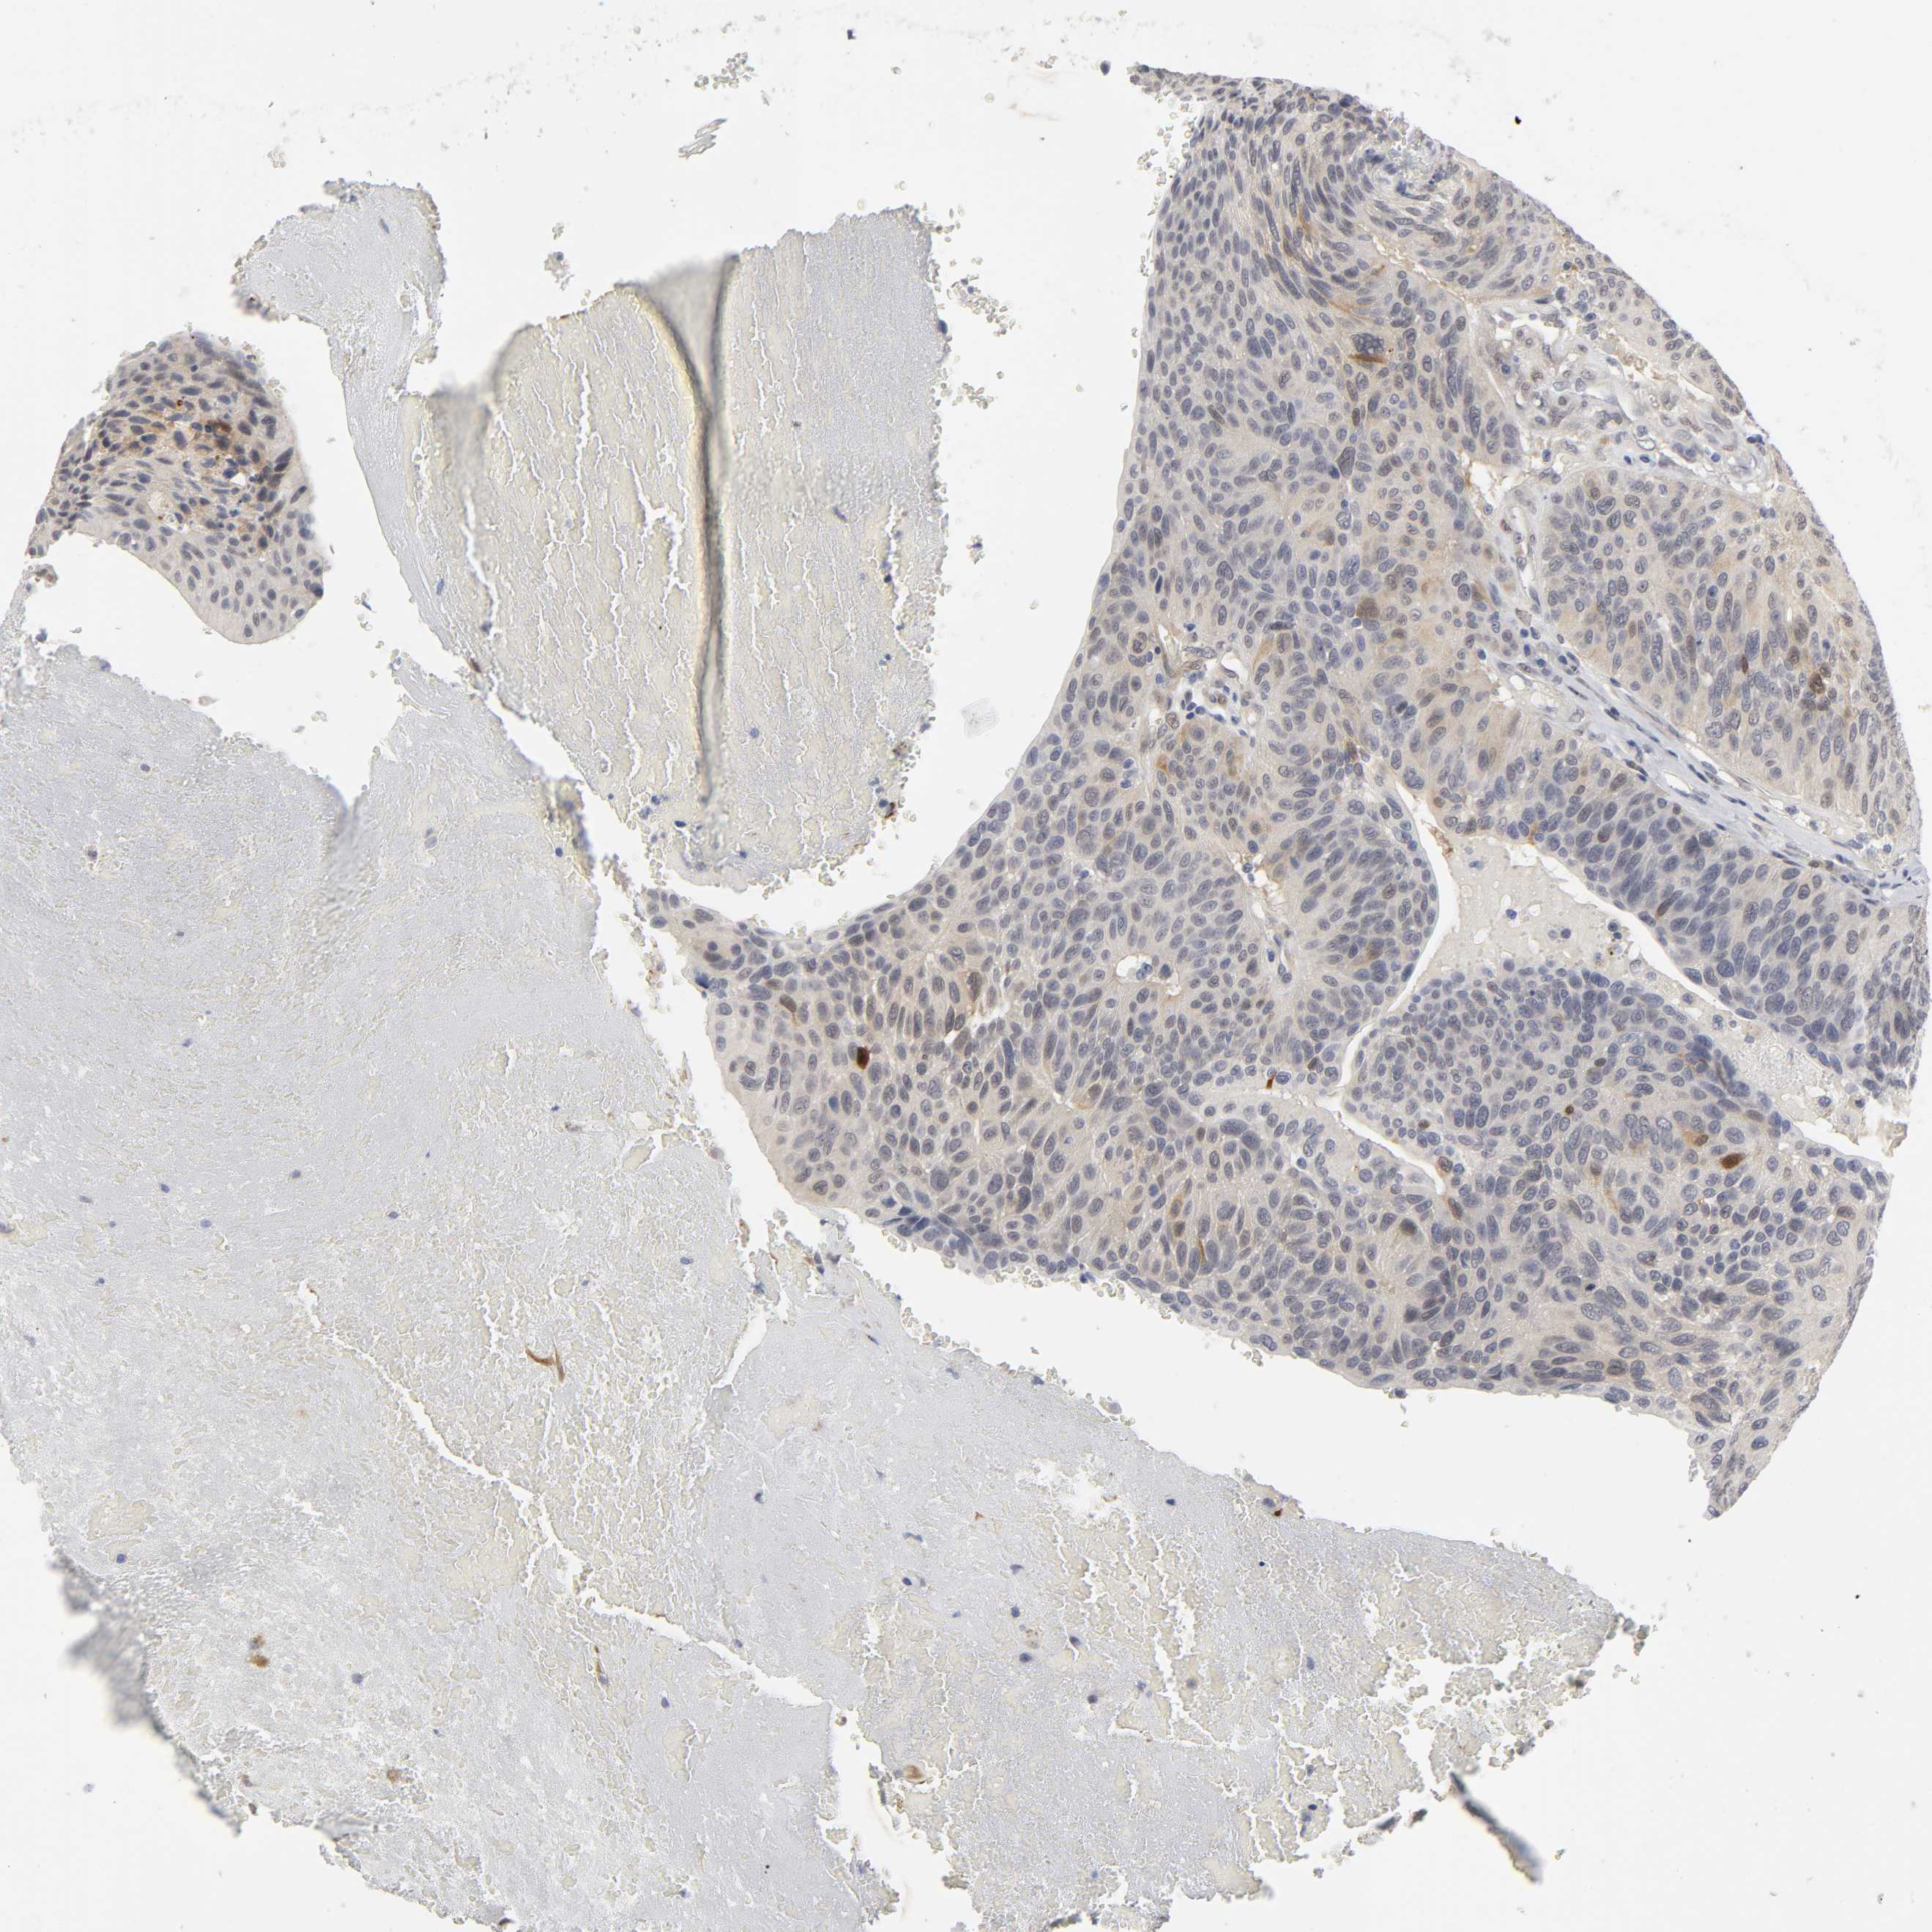

UROTHELIAL CANCER - Protein expressioni

A mouse-over function shows sample information and annotation data. Click on an image to view it in a full screen mode. Samples can be filtered based on level of antibody staining by selecting one or several of the following categories: high, medium, low and not detected. The assay and annotation is described here.

Note that samples used for immunohistochemistry by the Human Protein Atlas do not correspond to samples in the TCGA dataset.

Antibody stainingi

Antibody staining in the annotated cell types in the current human tissue is reported as not detected, low, medium, or high, based on conventional immunohistochemistry profiling in selected tissues. This score is based on the combination of the staining intensity and fraction of stained cells.

Each image is clickable and will lead to virtual microscopy that enables deeper exploration of all samples and also displays staining intensity scores, fraction scores and subcellular localization as well as patient and tissue information for each sample.

Antibody HPA004749

Staining

High

Medium

Low

Not detected

Intensity

Strong

Moderate

Weak

Negative

Quantity

>75%

75%-25%

<25%

None

Location

Nuclear

Cytoplasmic/membranous

Cytoplasmic/membranous,nuclear

Urothelial carcinoma, High grade

Urothelial carcinoma, Low grade